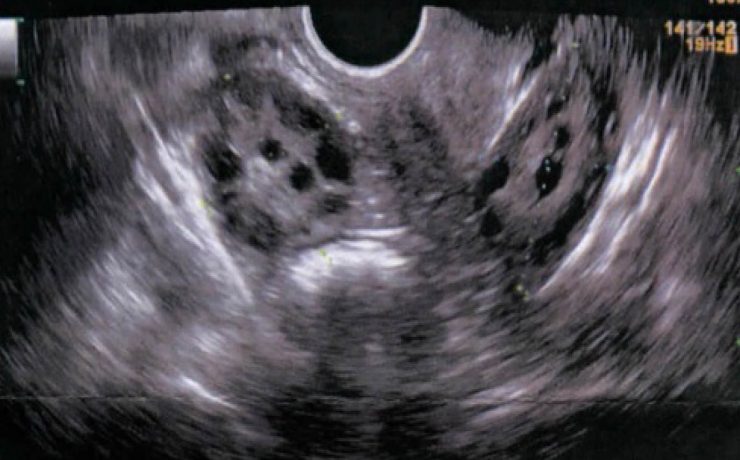

Aspectos ultrasonograficos del riñón

Los riñones órgano parque se encuentra en ambos lado de la columna vertebral dorso-lumbar, se sobreponen parcialmente en la parrilla costal baja y se sitúan retroperitoneales entra la 3ra y 6ta vertebra lumbares. Se dividen para su estudio en corteza, medula y seno; La densidad de su parénquima (medula y